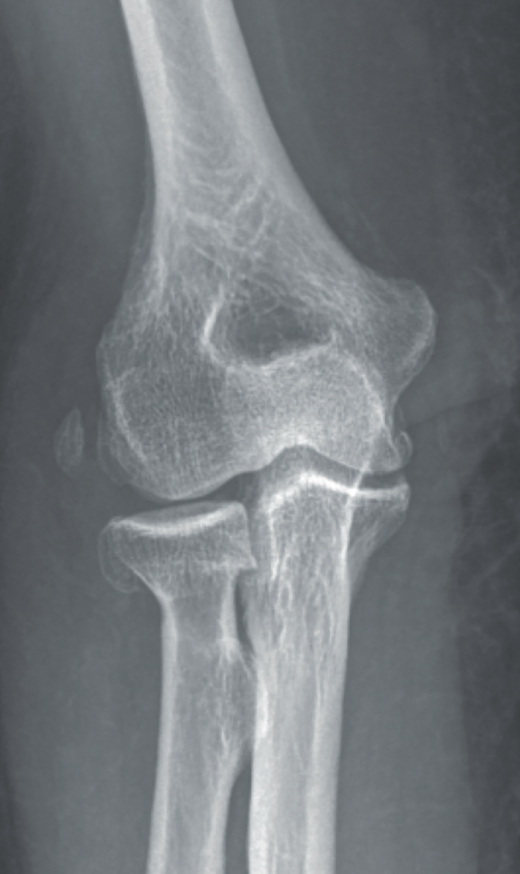

- Radiografía simple: puede orientarnos hacia una inestabilidad si se objetivan signos indirectos, tales como calcificaciones en la inserción ligamentosa, que sugieran antecedente de avulsión ligamentosa (Figura 7).

Signos de haber tenido fracturas en la cabeza del radio o la coronoides, aunque ya estén consolidadas, nos ponen en el contexto de un posible antecedente de luxación acompañando a las fracturas. También la presencia de fractura con fragmento cortical posterolateral del húmero, que ha sido considerado como el “Hill-Sachs del codo”(12)(Figura 8).